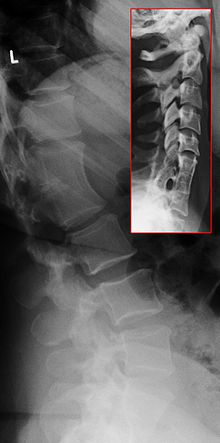

Le syndrome de Klippel-Feil ou SKF (en anglais, Klippel-Feil syndrome ou KFS) est une condition caractérisée par un défaut de segmentation des somites cervicaux, résultant en une fusion congénitale de vertèbres cervicales.

Aujourd'hui, n'importe quelle fusion congénitale d'au moins deux vertèbres est considérée comme une manifestation du syndrome de Klippel-Feil.